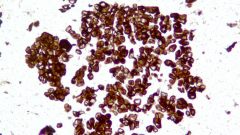

Description CLDN18.2是Claudin蛋白質家族的一員,位于細胞膜表面,Claudin18.2(CLDN18.2)表達具有特異性。其作為Claudins蛋白的一個亞型,在正常組織中僅表達于分化的胃黏膜上皮細胞。在胃癌、食管癌和胰腺癌等多種腫瘤中表達,并且不僅限于原發(fā)病灶,在轉移灶中也有表達。目前臨床研究中使用的檢測方法均為免疫組化。

IHC染色結果